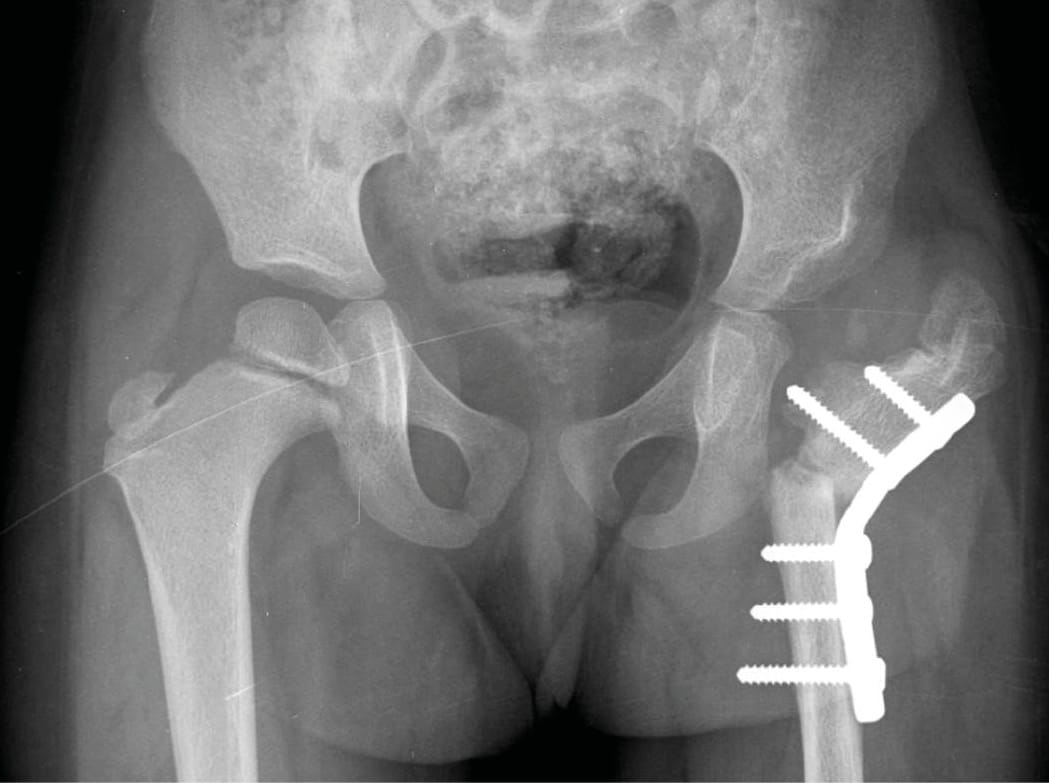

The patient underwent: Extensive surgical debridement and lavage, correction of hypo-albuminemia, Empirical post culture sensitive IV antibiotics, Valgus osteotomy of the proximal femur to improve joint mechanics and compensate for deformity (Figure 2).